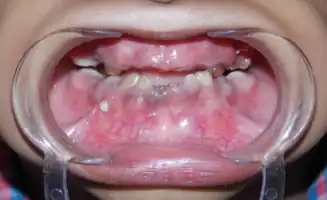

| Shows the severe underbite pattern that is a common development pattern in individuals with Tricho Dento Osseous Syndrome | |

In the oral cavity 100% of people diagnosed with TDO have taurodontism which is characterized by vertically enlarged pulp chambers at the expense of the roots of the teeth; the floor of the pulp chamber and furcation is moved apically down.[1] This is due to the failure of the Hertwig epithelial root sheath which maps the shape of the forming tooth roots during active differentiation. Amelogenesis imperfecta, an abnormal formation of the enamel or external layer of the crown of the tooth, may also be present where the tooth enamel may be thin or absent. There are several clinical subsets of amelogenesis imperfecta, but common to TDO is the hypoplastic-hypomaturation subtype;[3] the hypomaturation-hypoplastic is less common in individuals with TDO. The difference between the 2 dominant subtypes is the changes seen in the enamel matrix, and the phenotypic type that predominates. The hypoplastic-hypomaturation type of amelogenesis imperfecta with TDO occurs where the tooth enamel depicts a generalized pitted pattern, with open contacts between the teeth as well as an open bite. A smaller number of cases are of the hypomaturation-hypoplastic case type, in which the enamel structure is softer due to the under maturation of ameloblasts during development. Mandibular prognathism also called a severe underbite, is also a prominent feature in TDO. Prognathism defects are diagnosed based the level of severity that this condition interferes with being able to chew or speak properly.

Intra-oral view showing severly attrited teeth, visible pulp chambers and class III anterior occlusal relationship. -